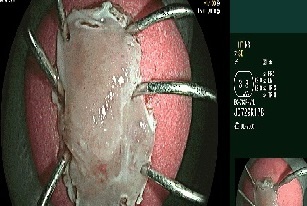

Ê-kíp mổ thuộc các bác sĩ khoa Ung bướu phối hợp cùng khoa Gây mê hồi sức thực hiện. Qua đường rạch nhỏ ở ổ bụng, phẫu thuật viên thắt các mạch máu trung tâm, sau đó dùng dụng cụ nội soi cắt bỏ đoạn đại tràng sigma có khối u dưới sự hỗ trợ của hệ thống nội soi 3D hiện đại. Tiếp đó, các bác sĩ nạo vét hạch xung quanh và khâu nối lại ruột để tái lập đường tiêu hóa.